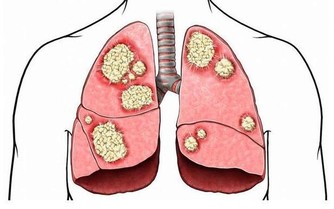

【引導語】水是生命之源,是我們離不開的!但是你真的會喝水嗎?別看喝水是件小事,喝不對也會帶來大麻煩。睡前不喝水小心腦血栓!揭十大奪命喝水惡習,你必須知道! 壞習慣一:自來水一燒開就喝。 國人喝白開水是種好習慣,但是你知道嗎?水不能一燒開就喝。因為我們的自來水都經過氯化消毒,其中氯與水中殘留的有機物結合,會產生鹵代烴、氯仿等多種致癌化合物。 中國農業大學食品科學與營養工程學院教授姜微波建議,燒水時,不妨採取三步走:首先將自來水接出來後先放置一會再燒;水快開時把壺蓋打開;最後,水開後等3分鐘再熄火,就能讓水裡的氯含量降至安全飲用標準,是真正的"開水"。 壞習慣二:飲水機從不洗。 桶裝水和飲水機無論在家庭還是辦公、公共場所都已非常普遍,你有沒有想過,用的飲水機自從放在那兒就再也沒「洗過澡」。 飲水機看似讓人喝上好品質的水,實則「二次污染」很嚴重。每當打開飲水機龍頭時,聽到「咕嚕」的聲音,桶裡翻出一串氣泡,這就是有空氣進入,灰塵及微生物就會被帶入。 據國家環境衛生監測部門檢測數據顯示,桶裝飲水機內的冷熱水膽3個月不洗就會大量繁殖細菌,如大腸桿菌、葡萄球菌等。所以,最好一月清潔一次,夏天兩週清潔一次。辦公室的飲水機因為使用頻繁,更得勤加清洗。 壞習慣三:愛喝瓶裝水。 攜帶方便、開蓋能喝,在中國,瓶裝水消費正在以每年30%的速度遞增。 國際食品包裝協會常務副會長董金獅卻指出,瓶裝水所使用的聚酯瓶往往含有可能導致人體慢性中毒的物質,尤其是當瓶子在高溫環境中,或開啟後沒及時喝掉,有害物質會滲入水中,危害健康。 因此,瓶裝水一定不能受熱或暴曬。「很多人喜歡在車裡放一箱水,這是不對的。尤其夏天,後備箱溫度非常高,容易讓有害物質進入水中。」董金獅建議,最好的辦法是買個質量好的水壺自己帶水,安全又環保。 壞習慣四:喝千滾水。 「現在用電熱水壺的家庭越來越多,很多人燒的水一次喝不完,過一會兒又重複燒開。這種千滾水最好別喝。」趙飛虹說,水燒開儘量當次喝完,別反覆加熱。 很多人擔憂飲水機中的水是不是千滾水,因材料限制,飲水機中水的最高溫度一般為九十攝氏度左右,達不到沸騰的狀態,不是千滾水。「但桶裝水的最佳飲用時間是出廠後1—15天,一旦超過15天,水中的細菌過多,就不宜再飲用。」 壞習慣五:不渴不喝水。 國內一項調查數據顯示,七成人都是發覺渴了才喝水。殊不知當你感到口渴的時候,你的身體至少已經流失了1%的水分。 喝水不是為瞭解渴,而是讓其參與新陳代謝,被人體吸收,長時間缺水會增加血液的黏稠度,誘發心腦血管疾病。同時,越不注意喝水,喝水的慾望就會越低,人就會變得越來越「乾旱」。 所以,不管渴不渴都要及時補水。外出時手裡帶上一瓶水,隨時喝一口;辦公室或家裡多放上幾個水杯,見縫插針,有機會就喝。 壞習慣六:每天喝不夠6杯水。 上班一族常常會因工作關係疏忽了喝水,長此下去,膀胱和腎都會受損害。 《中國居民膳食指南》建議,在溫和氣候條件下生活的、輕體力活動的成年人,建議每天最少飲水1200毫升,大約6杯的量。如果活動量大,出汗多,則相應增加喝水量,及時補水。 有人會問,之前一直說每天喝水不少於2000毫升也就是8杯水,為什麼現在只有1200毫升?其實,2000毫升是指人一天需要的水分總量,果蔬裡含有大量水分,連主食、肉裡都有,人體需要的水,很大一部分來自於食物中。 6杯是最低限的量,有些人則需要喝得更多。比如煩躁的人多喝水能舒緩心情,肥胖的人多喝水能保持體重,運動後、洗澡後也都要及時補充水分。 壞習慣七:不按體質喝水、飲料代水。 「白開水沒味,還是喝飲料吧。」很多孩子每天可樂、果味飲料不離手,用飲料代水,無異於花錢買身病。「不但起不到給身體補水的作用,還會降低食慾,影響消化和吸收。」趙飛虹說。 如果一定要喝有味兒的水,也要根據自身體質,適當改善。比如—— 便秘的人可以喝點蜂蜜水或者果蔬汁,能夠促進腸道蠕動;胃寒的人要少喝性寒的綠茶、涼茶、果汁,多喝暖胃的紅茶、薑糖水。 三杯「長命水」。 救命水,不是真的喝了就能救命,而是這種飲水方式會給健康帶來極大的好處,堅持喝有延年益壽的功效。 壞習慣八:晨起不喝水,到老都後悔。 早上起來的第一杯水是真正意義上的救命水,中老年人更應該注意。 人體經過一夜代謝之後,身體的所有垃圾都需要洗刷一下。飲用一杯水可降低血液黏度,增加循環血容量。 早晨這杯水最好選以下三種: 第一種是清澈的水,白開水、礦泉水皆可,能夠降低人體血液黏稠度。 第二種是檸檬水,檸檬酸能夠提升早晨的食慾。 第三種是淡鹽水,它對便秘的人非常有益。 壞習慣九:吃咸了不馬上補水。 吃太鹹會導致高血壓,也可導致唾液分泌減少、口腔黏膜水腫等。 如果吃咸了,首先要做的就是多喝水,最好是純水和檸檬水,儘量不要喝含糖飲料和酸奶,因為過量的糖分也會加重口渴的感覺。 淡豆漿也是一種很好的選擇,其中90%以上都是水分,而且還含有較多的鉀,可以促進鈉的排出,且口感比較清甜。 壞習慣十:睡前不喝水。 睡前不宜喝太多水,但可以稍微抿上兩口,尤其是老人。 當人熟睡時,由於體內水分丟失,造成血液中的水分減少,血液黏稠度會變高。 臨睡前適當喝點水,可以減少血液黏稠度,從而降低腦血栓風險。 此外,在乾燥的秋冬季節,水還可以滋潤呼吸道,幫助人更好的入睡。 【編後語】水看上去清澈潔淨,但一樣有微生物、有害物質藏身,無論喝桶裝水、瓶裝水還是自己燒的水,都要儘量避免以上幾個壞習慣。千萬別讓我們賴以生存的水變成阻礙我們健康的兇手。